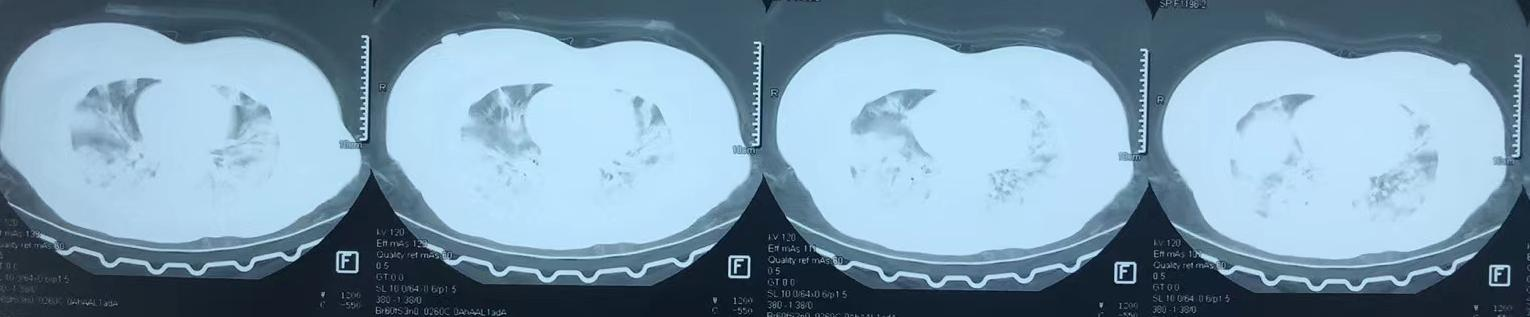

据悉,34岁的患者史某于1月中旬出现发热、咳嗽,初期考虑为“普通感冒”,在当地医院治疗一周后病情加重,肺部CT提示双肺病变,1月21日转入湘雅三医院急诊,因“呼吸衰竭”行气管插管呼吸机辅助呼吸后转入内科ICU,呼吸与危重症医学科刘纯主任医师团队立即开展救治。

重症肺炎患者,病原体不明,刘纯凭借多年的呼吸危重症抢救经验,积极迅速地收集临床资料、完善相关检查,很快锁定病原体——乙型流感病毒。但由于抗病毒时机太晚,治疗效果欠佳,紧接着并发耐药细菌感染,肺部情况反复恶化,多次生死一线。在多学科MDT合作下,团队为患者制定了周密严谨的个性化治疗方案。

经过1个多月的严密监测与抢救,患者病情日渐好转,顺利出院。患者高兴地告诉我们,老公、儿女、父母、哥哥、朋友等都在家里,准备了大餐等着她回家,今天她们家过大年。